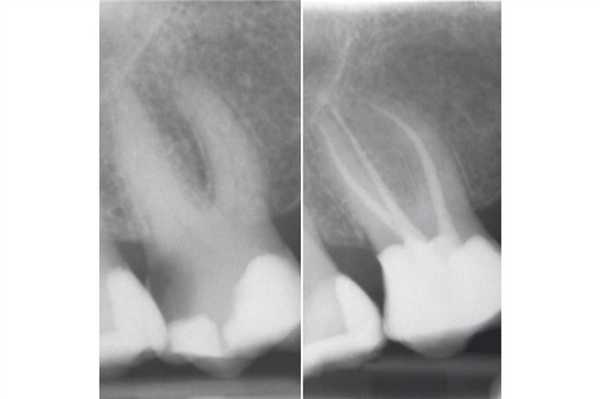

Непрямые реставрации с адгезивным механизмом фиксации являются довольно частым выбором врачей-стоматологов, учитывая их эстетичность и консервативность. Данный тип реставраций также способствует сохранению большего объема тканей зуба. Однако при фиксации подобных конструкций необходимо контролировать уровень влажности рабочего поля, дабы не компрометировать силу бондинговой связи. Удаление излишков композитного цемента часто может вызвать кровотечение с поддесневой области, и таким образом нарушить весь адгезивный протокол. В долгосрочной перспективе такие последствия ассоциированы с эффектом микроподтекания и расцементировки коронки. DME может помочь решить подобные проблемы и оптимизирует условия для фиксации коффердама (фото 1).

Фото 1. Повторное эндодонтическое лечение и фиксация E.max накладки на зуб LR6 a) Рентгенограмма до ревизии канала. b) Повторное лечение корневого канала и формирование композитной культи. Пациент был направлен к своему лечащему стоматологу для выполнения реставрации с перекрытием бугров. с) Препарирование под накладку; дистальный край сформирован на композитной основе. d) Изоляция коффердама перед фиксацией. e) Изолирование соседних зубов при помощи тефлоновой ленты. f) Фиксация накладки на композитный цемент. g) Очистка излишков цемента. h) Вид после фиксации.

DME менее важен при использовании традиционных цементов (цинк-фосфатных или СИЦ) для фиксации непрямых реставраций. Данные материалы мене чувствительные к промахам изоляции, а их излишки могут быть удалены после полной полимеризации. Однако в подобных случаях достаточно сложно получить качественный оттиск (фото 2).

Фото 2. Лечение корневых каналов и формирование композитной культи на зубе LL6. Пациент был направлен к лечащему врачу для изготовления накладки с перекрытием бугров. Золотая накладка была зацементирована на Fuji Plus. Дистальный край находился под десной, а край накладки был сформирован на композитной реставрации (DME). Граница препарирования на всех поверхностях находилась в границах тканей зуба, кроме дистальной поверхности. Рентгенограмма, полученная через год, демонстрирует признаки заживления периапикального поражения.

Почему DME важно для эндодонтии?

В эндодонтии врачи часто встречаются с зубами, один из краев дефекта которых находиться глубоко под деснами. По сути, DME дает шанс зубу «выжить», ведь без подобного подхода такой зуб можно категоризировать как такой, что не подлежит восстановлению (фото 7). Эффективное восстановление глубокого края дефекта часто является наиболее сложной частью лечения и занимает больше всего клинического времени.

Фото 7. Пациент обратился за стоматологической помощь по поводу кариеса корня и возможности восстановления зуба LR6. В ходе первого визита был очищен весь кариес и удалена старая пломба, после чего приступили к DME. Эндодонтическое лечение проводили в ходе второго визита. В дистальный канал установили стекловолоконный штифт, а всю дистальную поверхность восстанавливали посредством композита. Пациент был направлен к лечащему врачу для изготовления непрямой реставрации.